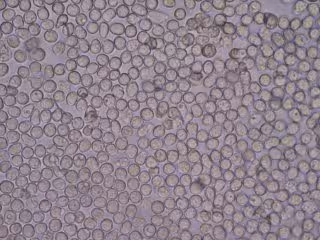

Genes que regulan los glóbulos blancos alterados, relacionados con la genética y

Genes que regulan los glóbulos blancos alterados, relacionados con la genética y - BOBJGALINDO/WIKIMEDIA COMMONS - Archivo